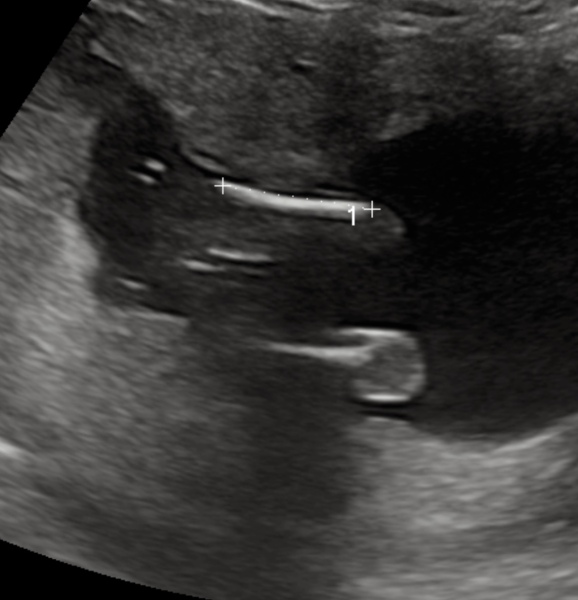

Dorisxxxxx · 25/04/2023 18:05

What does everyone think of my potty shot? Was told female but don't see the '3 white lines'